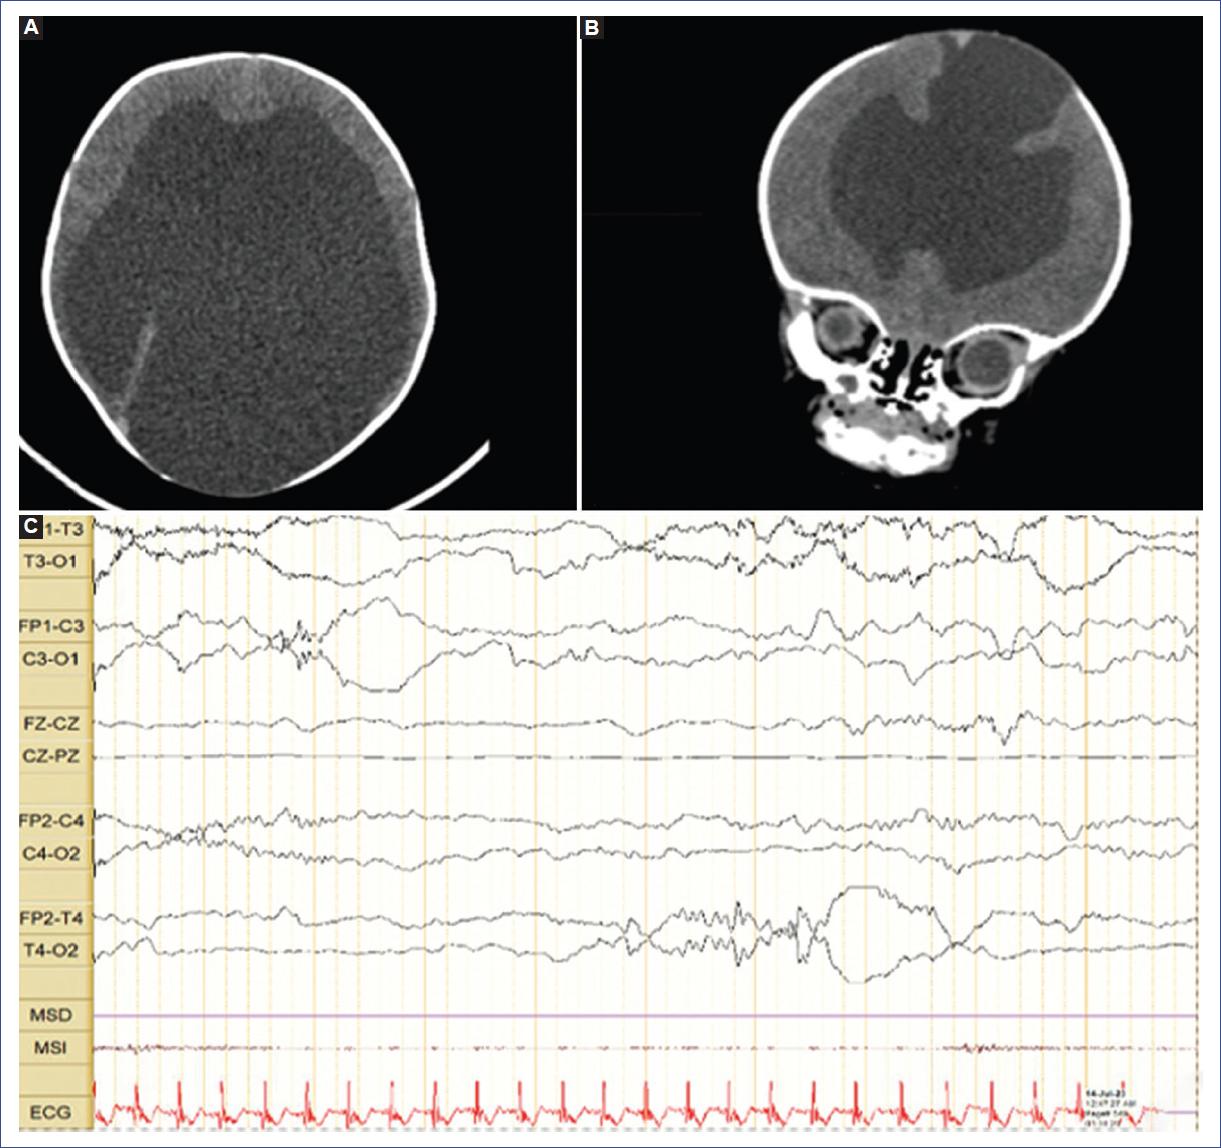

Recién nacido de sexo masculino, hijo de madre de 26 años, G1C1V1, de alto riesgo por embarazo gemelar bicorial y biamniótico. En el gemelo 1 se hizo diagnóstico prenatal de macrocránea y ventriculomegalia. Estudio de TORCH negativo. Nace a las 34.5 semanas de gestación por vía cesárea ante el inicio prematuro de trabajo de parto y por trastorno hipertensivo del embarazo. Al nacimiento, peso de 2920 gramos, talla de 46 cm y perímetro cefálico de 45 cm (Z: + 9.29 SD Fenton). Durante la adaptación requiere oxígeno a flujo libre por no cumplir las metas de oximetría de pulso y presentar cianosis con Apgar de 7, 9 y 10 a 1, 5 y 10 minutos, respectivamente. Al inicio con mal manejo de secreciones, requiriendo aspiración frecuente en los primeros minutos de vida. En la exploración física destaca macrocránea con fontanelas amplias normotensas. En la primera evaluación con ecografía transfontanelar se describe un gran aumento en el volumen del sistema ventricular, con desviación del septo interventricular a la derecha e importante disminución del espesor del parénquima cerebral. Hay aparente hipoplasia del parénquima cerebeloso. Al tercer día de vida se realiza una TC de cráneo simple que reporta trastorno de la migración neuronal con extensa esquizencefalia de labio abierto, asociada a hidrocefalia, disgenesia/agenesia del cuerpo calloso y marcada alteración de las estructuras de la fosa posterior (Fig. 3 A y B). No se pudo realizar RM cerebral para confirmar los hallazgos tomográficos y posibles diagnósticos diferenciales. Presentó crisis epilépticas desde el primer día de vida, con necesidad de tratamiento anticonvulsivante intravenoso con fenobarbital a dosis de 15 mg/kg/dosis en de impregnación y con mantenimiento de 5 mg/kg/día. Se realizó monitorización videoelectroencefalográfica, que fue anormal por atenuación de los ritmos de fondo esperados para la edad y lentificación de estos, compatible con un grado de encefalopatía moderado a grave, y además correlacionados con signos de atrofia cortical o compromiso estructural craneal, con evidencia de descargas aisladas e irregulares de onda aguda y punta onda lenta de mediana amplitud que se producen de manera intermitente con zonas de mayor compromiso frontocentral bilateral con actividad irritativa focal en esta localización (Fig. 3C). Por difícil control de las crisis requirió reimpregnación con fenobarbital a dosis de 20 mg/kg, ajustando el mantenimiento a 7.5 mg/kg/día, y se adicionó levetiracetam a dosis de 30 mg/kg/día, logrando el control de las crisis. Además, presentó un aumento del perímetro cefálico por encima de 2 desviaciones estándar para su edad, que requirió derivación ventriculoperitoneal. Fue valorado por oftalmología, con único hallazgo de papila hipoplásica con indicación de seguimiento ambulatorio. Inició terapia de rehabilitación y logró adecuada succión. Con esto y el control de las crisis, fue egresado con recomendaciones de seguimiento multidisciplinario.

Figura 3 Caso 3. A y B: tomografía computarizada de cráneo simple, cortes axial y sagital. Se observan esquizencefalia de labio abierto con compromiso de la región parietooccipital derecha (A) e hidrocefalia grave asociada con marcada disminución de volumen de la corteza cerebral (B). C: electroencefalograma con actividad interictal aislada e irregular en forma de ondas agudas y punta onda lenta de mediana amplitud, con mayor compromiso frontocentral bilateral y temporal derecho.